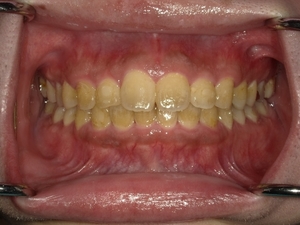

すきっぱ(空隙歯列)CASE7 2023.08.28 20代男性☆Before→After☆〇ご相談内容:前歯真ん中の隙間があいている〇矯正の種類:マウスピース型矯正「インビザラインGO」〇治療期間:19週間〇治療費用:44万円(税込) < すきっぱ(空隙歯列)CASE8すきっぱ(空隙歯列)CASE6 > ブログ記事一覧をみる